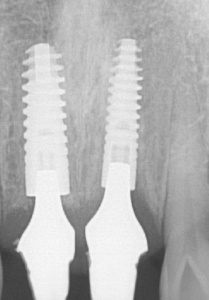

수술 후 2개월 뒤 설콘 지대주 상태

상처는 잘 아물었고, 특별한 염증소견없이 2개월 만에 골융합이 충분히 완성되었습니다.

이 분에게 적용한 앵킬로스 임플란트는 국산임플란트보다 골융합 속도가 빨라서 2개월 차에 치료 마무리가 가능했습니다. 그리고 치아색상은 주변의 치아색상과 조화를 이루어서 완성했습니다.

임플란트가 잘 고정된 상태